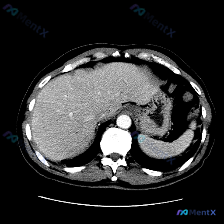

预设疑问: 图像中观察到的具体异常是什么?脾脏病变

影像资料: 单张腹部增强CT(轴位软组织窗)+ 正式影像分析报告

- 肝脏: 形态自然,密度均匀,血管走行自然,未见明显异常占位或扩张。

- 脾脏(重点看这里!): 位于左上腹,形态、大小正常,实质密度均匀,未见外伤性裂伤、梗死或占位性病变。

- 其他: 胰腺、肾上腺、腹主动脉、腹膜后淋巴结、胃、腹腔、腹壁、骨骼等,该层面均未见明显病理性改变。